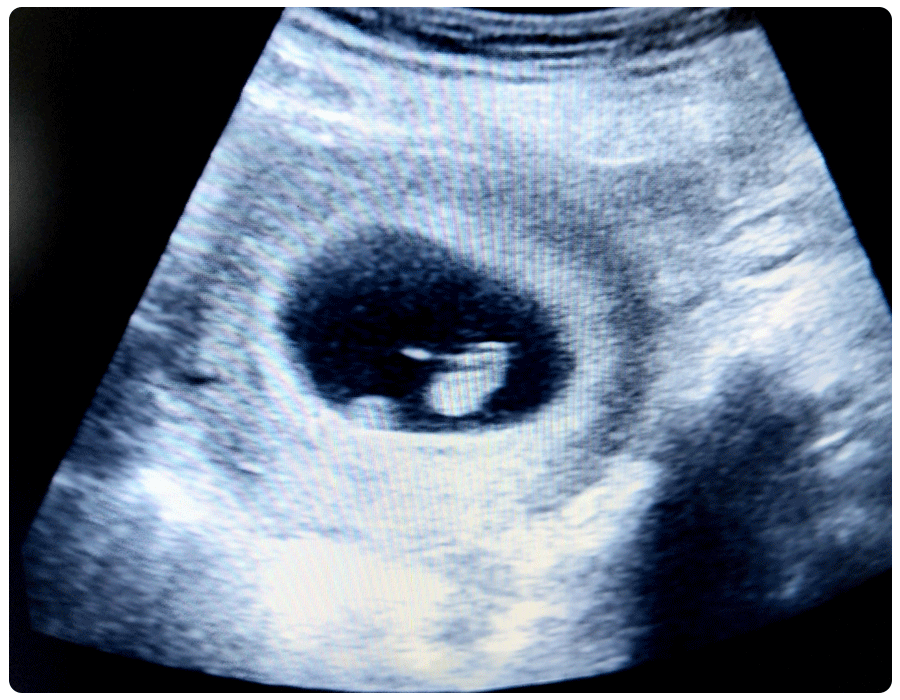

6 week ultrasound pictures

This is what a typical 6 week ultrasound looks like:

Unless you have a medically trained eye, you won’t be able to identify much. To patients, the pregnancy will probably resemble a peanut at a 6 week ultrasound, says Talib.

Your ultrasound technician or practitioner’s trained eye will be able to identify a gestational sac (a fluid-filled pouch that’ll eventually become the amniotic sac), a yolk sac (a temporary structure that helps the pregnancy grow) and an embryo. “This is before any recognizable organs or limbs have developed,” says Toland. Your doctor will also check for ovarian cysts and uterine fibroids, Talib adds.